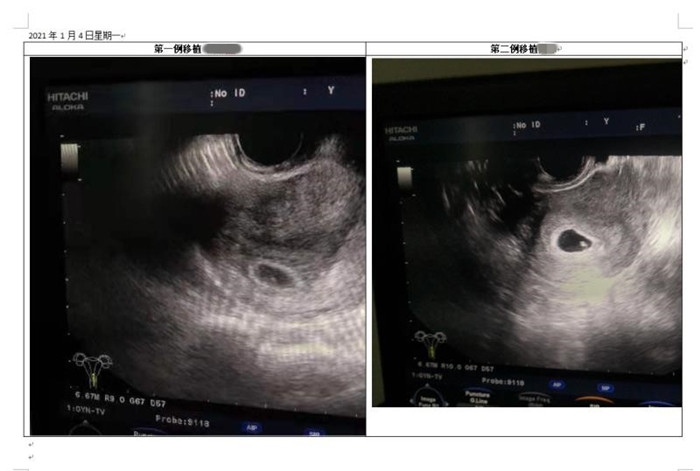

得知我院生殖醫(yī)學(xué)中心獲批開展“試管嬰兒”技術(shù)后,侯女士和黃女士都決定要一個“試管寶寶”。經(jīng)過前期準(zhǔn)備,2020年12月7日,兩人同時進(jìn)行“取卵”手術(shù),12月10日進(jìn)行胚胎移植,12月21日抽血HCG值明顯升高提示懷孕,2021年1月4日B超顯示宮內(nèi)妊娠、看到胎心,兩人同時傳出喜訊,第一次試管就迎來了“心肝寶貝”。

B超提示宮內(nèi)妊娠、可見胎心